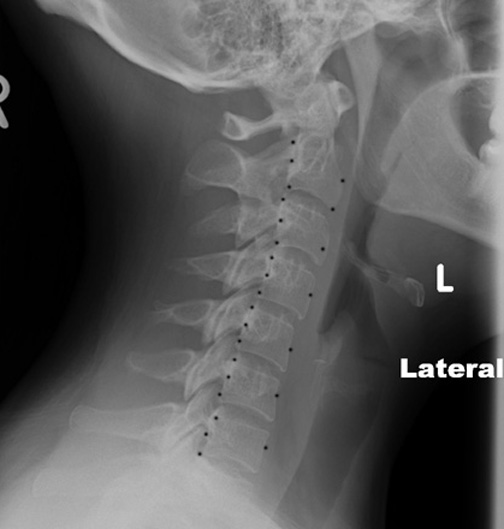

Identify the retrotracheal and retropharyngeal space. Click the image for labeling.